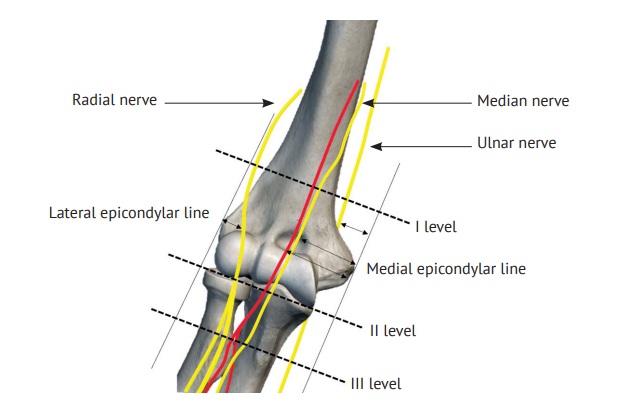

Первым этапом определяли кратчайшее расстояние от лучевого нерва до плечевой и лучевой костей и от срединного нерва до плечевой и локтевой костей при разных функциональных положениях верхней конечности в ЛС. Измерения выполнялись на трех уровнях: I уровень — на 5 см выше суставной щели; II уровень — на уровне сустава; III уровень — на уровне шейки лучевой кости (рис. 1).

Рис. 1. Схема анатомических образований на трех уровнях в области локтевого сустава (вид спереди)

По ангиорентгенограммам в прямой проекции на II уровне в положении полного разгибания изучались расстояния от условной латеральной эпикондилярной линии (УЛЭЛ) до лучевого нерва и от условной медиальной эпикондилярной линии (УМЭЛ) до срединного нерва и плечевой артерии (рис. 3). Данный этап исследования был необходим для определения безопасных зон, в которых повреждение сосудисто-нервных образований сведено к минимуму, так как II уровень является наиболее удобным для расположения артроскопических портов.

Затем определяли безопасные интервалы возможного смещения порта от надмыщелков плечевой кости во фронтальной плоскости на II уровне, так как именно этот уровень наиболее удобен для проведения релиза поврежденных сухожилий. При изучении расстояний от УЛЭЛ до лучевого нерва и от УМЭЛ до срединного нерва и плечевой артерии по ангиорентгенограммам на II уровне определено, что лучевой нерв располагается на расстоянии 15,8 (15,6–16,0) мм, срединный нерв отдален от УМЭЛ на 17,5 (16,6–18,1) мм, а плечевая артерия — на 22,4 (20,5–22,8) мм.

С точки зрения удобства работы с поврежденными сухожилиями разгибательной и сгибательной групп мышц предплечья наиболее подходящим является II уровень. Определены расстояния от надмыщелков до важных сосудисто-нервных образований:

1) для латерального порта зона расположена не более чем на 15 мм от УЛЭЛ, при смещении более 15 мм увеличивается риск травматизации лучевого нерва;

2) для медиального порта зона ограничена 15 мм от УМЭЛ, при увеличении данного расстояния возрастает риск повреждения плечевой артерии и срединного нерва.